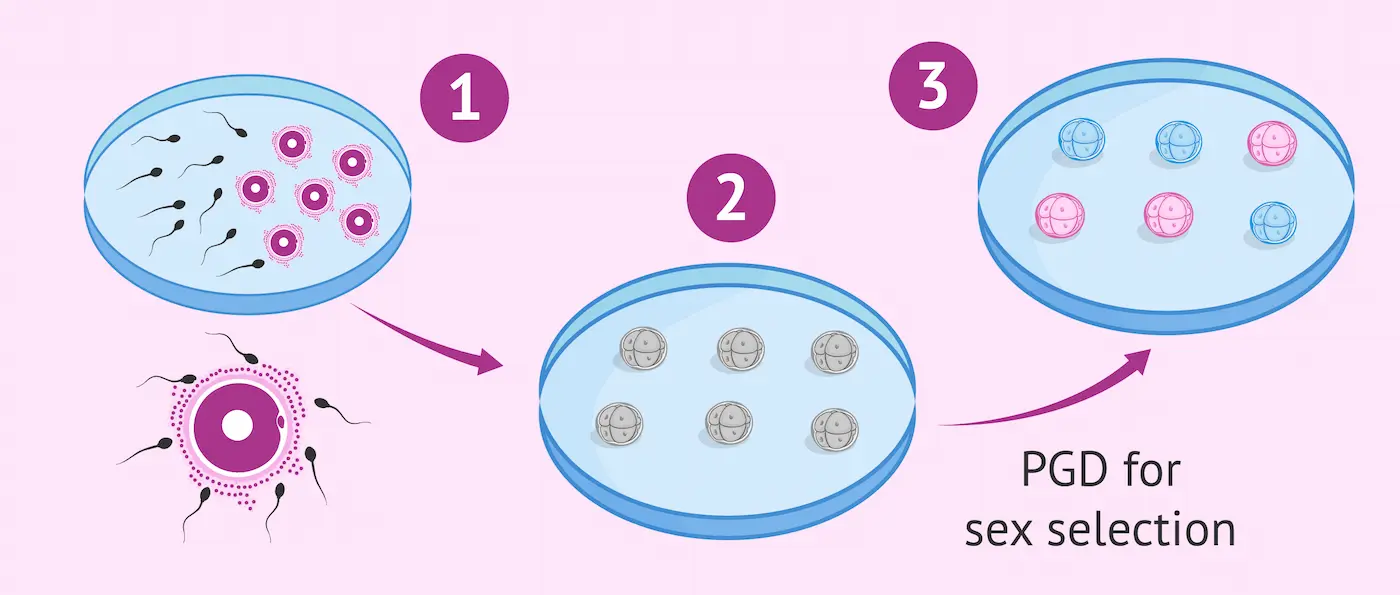

Can You Choose Gender With IVF? A Simple Guide to IVF Gender Selection

Modern fertility treatments give intended parents more options than ever before. One of the most discussed topics in reproductive medicine…